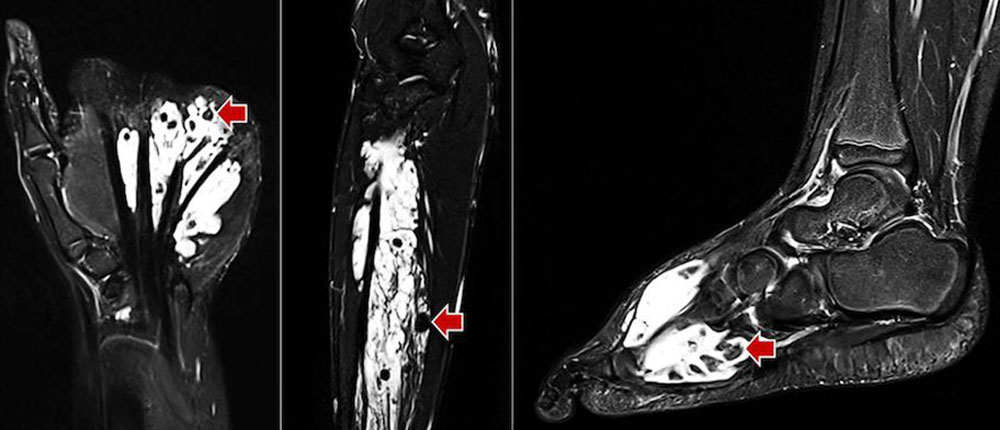

Venous malformation: In T2-weighted sequences, a strongly hyperintense signal predominates, which is highly visible on fat-suppressed T2-weighted sequences (STIR). Here they appear as septated, lobulated sponge-like or tubular masses, but often without any real space-occupying effect. Usually, venous malformations are isointense to the surrounding musculature on non-enhanced T1-weighted sequences. Spherical structures within the lesion with low signal on all sequences correspond to thrombi or calcified phleboliths which are pathognomonic for venous malformations when intralesional. Fluid-fluid levels can also be observed due to sedimentation phenomena within the venous malformations, but these are less frequent than in lymphatic malformations. After application of contrast medium, venous malformations slowly enhance contrast medium homogeneously. The average time to full contrast agent enhancement is about 90 seconds, which is significantly longer than for arteriovenous malformations (< 5 seconds). In contrast to arteriovenous malformations, in venous malformations the arteries supplying the affected extremity are not dilated. Flow voids are missing in venous malformations. Therapy-relevant venous connections (communicating veins) between the venous malformation and the deep venous system are occasionally identifiable on MRI. Abnormalities such as aplasia or hypoplasia of the deep and superficial venous system are also detectable.

Arteriovenous malformation: The morphologic correlate of the arteriovenous malformation, the so-called nidus (network of direct arteriovenous shunts), is often very hard to detect on native MRI sequences as a solid component is missing in AVMs. Occasionally, the AVM is surrounded by edema or connective and fatty tissue. Typically, spin-echo sequences (T1 or T2) show flow voids within the vessel channels because of high flow velocity. Diagnosis can ultimately be made with the help of dynamic MR angiography with high spatial and temporal resolution. Here, the nidus and the dilated, draining veins are contrasted almost immediately via the corkscrew-like dilated arterial feeders. In lesions located in the extremities, the inflowing and outflowing vessels are usually significantly enlarged compared to the unaffected side. In some cases the vessels are degenerated and show aneurysmal dilatations (so-called flow-related aneurysms). On account of the shunt with low flow resistance, normal vessel sections distal to the shunt may no longer be visible on MRA because of a steal phenomenon. The tissue surrounding the nidus typically does not show contrast enhancement and is hardly recognizable as the actual lesion since the lesion lacks a solid component. However, after invasive procedures or during an inflammatory or proliferative phase, surrounding edema with contrast enhancement is occasionally visible.